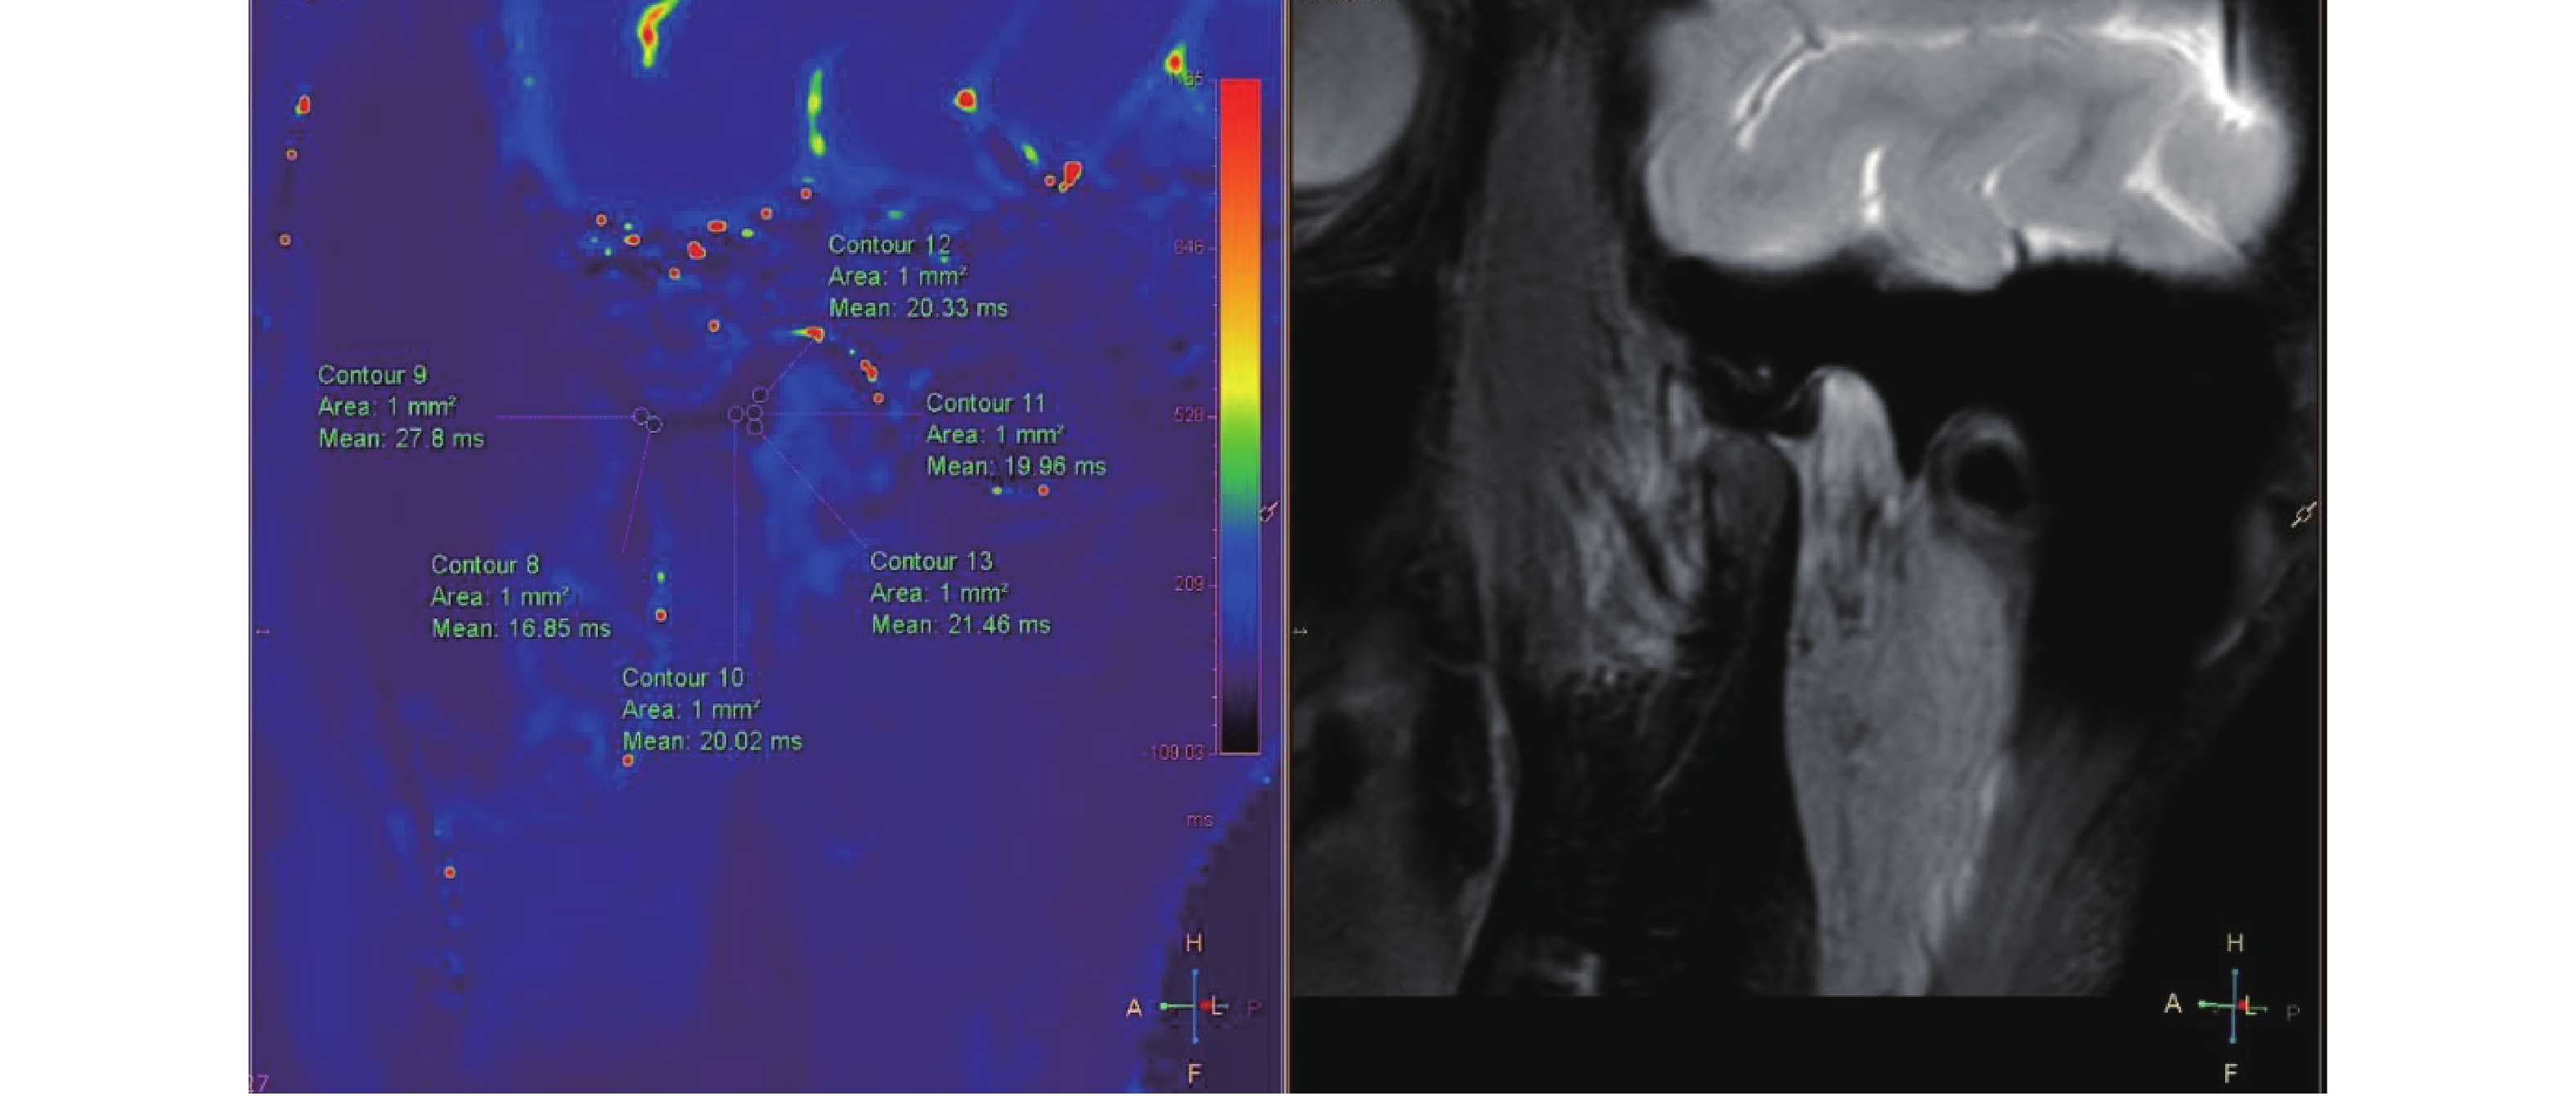

Correlation between T1-mapping and Feature Tracking in Hypertrophic Cardiomyopathy

Yan ZHANG, Lei YANG, Na LI, Mingjie PANG

2026, 47(4): 75-82. doi: 10.12259/j.issn.2095-610X.S20260409

Abstract:

Objective  To explore the correlation between T1-mapping and feature tracking in patients with Hypertrophic Cardiomyopathy (HCM).   Methods  Cardiac magnetic resonance (CMR) data were retrospectively collected from 86 HCM patients hospitalized at Yunnan Provincial First People's Hospital between January 2016 and July 2021. The differences in T1 values before and after contrast enhancement, extracellular volume (ECV), longitudinal strain (LS), circumferential strain (CS), radial strain (RS), and strain rate parameters were compared between the late gadolinium enhancement (LGE)-positive group (59 cases) and LGE-negative group (27 cases).   Results  (1) Patients in the LGE-positive group were younger with a higher proportion of NYHA class III-IV, larger end-diastolic maximal wall thickness, and greater left ventricular mass index (P < 0.05); (2) Pre-contrast T1 values were higher in the LGE(+) group compared to the LGE(-) group, and ECV values were elevated in the LGE-positive group (P < 0.05); (3) In the LGE-positive group, global longitudinal strain (GLS) showed negative correlations with left ventricular mass index, left ventricular end-diastolic maximal wall thickness, LGE%, T1 value, and ECV (r = −0.418, P = 0.008; r = −0.711, P = 0.021; r = −0.621, P = 0.015; r = −0.372, P = 0.020; r = −0.583, P = 0.010, respectively).   Conclusion  In HCM patients with myocardial enhancement, GLS is reduced in LGE-positive cases, which shows significant negative correlations with left ventricular end-diastolic volume, left ventricular mass index, end-diastolic maximal wall thickness, LGE%, and pre-contrast T1 value and ECV.